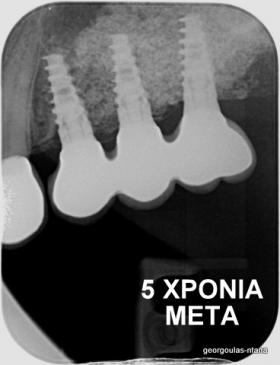

ΑΝΟΙΚΤΗ ΑΝΥΨΩΣΗ ΙΓΜΟΡΕΙΟΥ Κ ΤΟΠΟΘΕΤΗΣΗ 3 ΕΜΦΥΤΕΥΜΑΤΩΝ

Στην ασθενή αυτή πραγματοποιήθηκε ανοικτή ανύψωση ιγμορείου άνω αριστερά. Σε πρώτη φάση πραγματοποιήθηκε η οστική αύξηση και 6 μήνες μετά τοποθετήθηκαν 3 εμφυτεύματα. Τόσο στην πανοραμική όσο και στην τομογραφία κωνικής δέσμης (CBCT) που πραγματοποιήθηκαν 6 μήνες μετά την ανύψωση είναι εμφανής ο σχηματισμός οστού. Η τελευταία ακτινογραφία και φωτογραφία λήφθηκαν 5 χρόνια μετά την προσθετική αποκατάσταση.